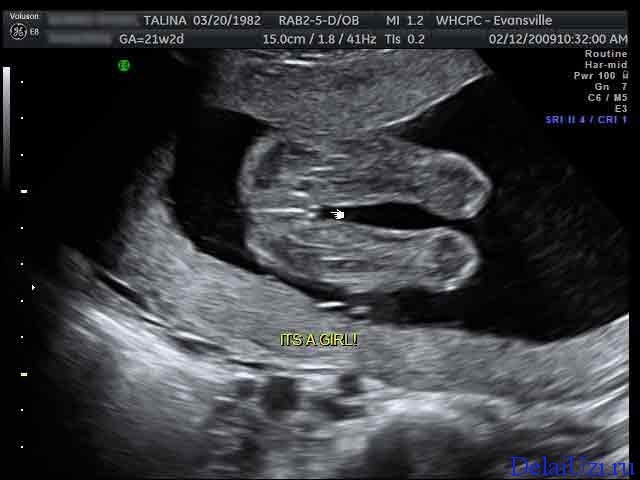

• Хто там є?

Хто там є?

Ось і знову час УЗД. Жінка іде трохи занепокоєна,бо зараз вона дізнається стать свого малюка.